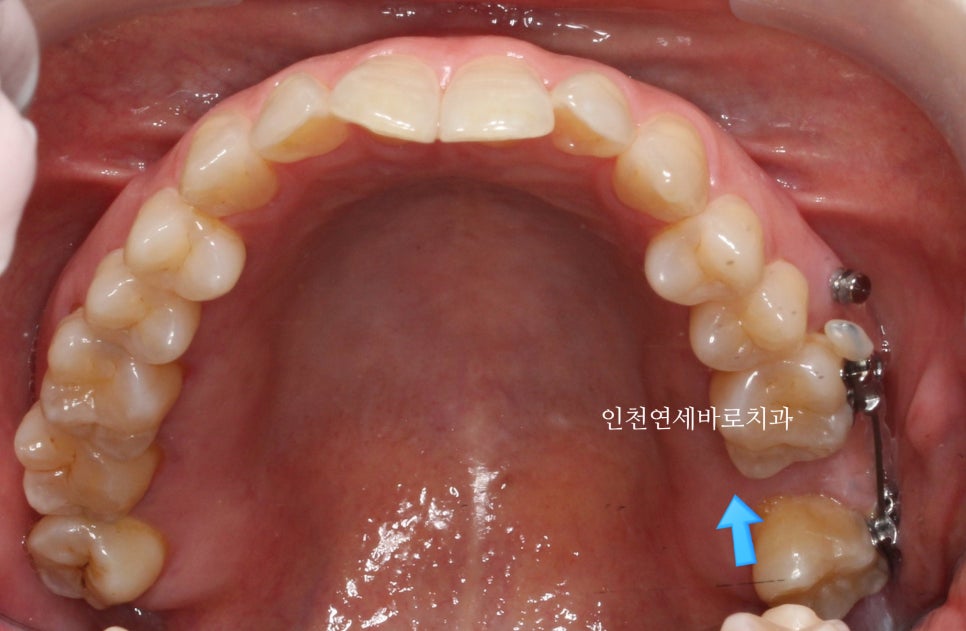

미니스크류를 사진에는 하나만 보이지만 두개 심었고,

계속 당겼습니다

사랑니이기 때문에 형태도 약간은 이상했지만 아래쪽과 교합도 문제없게 만들어드렸습니다.